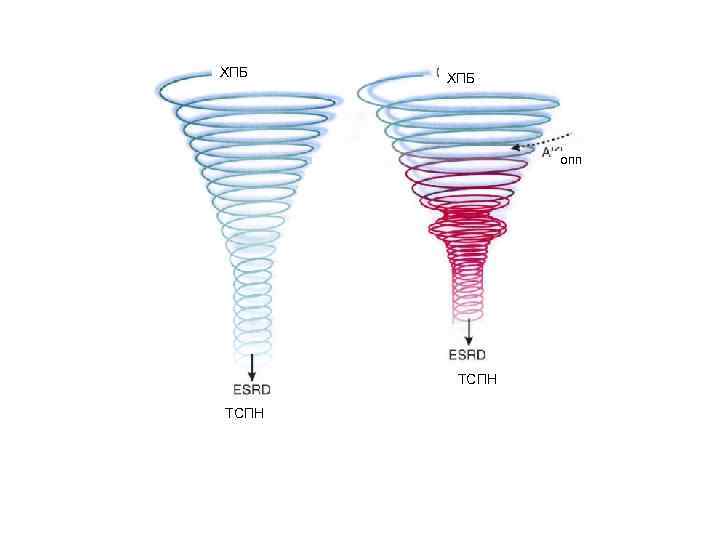

Понятие «Хроническая почечная недостаточность» подразумевало, что вначале в течение многих пациента у пациента было хроническое почечное заболевание, а потом развивалась хроническая почечная недостаточность, которая соответствовала по сути терминальной стадии поражения почек Диагноз «Хроническая болезнь почек» (даже при отсутствии снижения СКФ) подразумевает неизбежное дальнейшее прогрессирование процесса и призван привлечь внимание врача. Именно потенциальная возможность утраты функции почек является важнейшим моментом в понимании термина «хроническая болезнь почек» .

Понятие «Хроническая почечная недостаточность» подразумевало, что вначале в течение многих пациента у пациента было хроническое почечное заболевание, а потом развивалась хроническая почечная недостаточность, которая соответствовала по сути терминальной стадии поражения почек Диагноз «Хроническая болезнь почек» (даже при отсутствии снижения СКФ) подразумевает неизбежное дальнейшее прогрессирование процесса и призван привлечь внимание врача. Именно потенциальная возможность утраты функции почек является важнейшим моментом в понимании термина «хроническая болезнь почек» .

«Хроническая болезнь почек» может быть и обобщающим термином и самостоятельным диагнозом. Несмотря на многообразие этиологических факторов, большинство хронических заболеваний почек имеют единый механизм прогрессирования, а морфологические изменения в почках при почечной недостаточности однотипны и сводятся к преобладанию фибропластических процессов с замещением функционирующих нефронов соединительной тканью и сморщиванию почек.

«Хроническая болезнь почек» может быть и обобщающим термином и самостоятельным диагнозом. Несмотря на многообразие этиологических факторов, большинство хронических заболеваний почек имеют единый механизм прогрессирования, а морфологические изменения в почках при почечной недостаточности однотипны и сводятся к преобладанию фибропластических процессов с замещением функционирующих нефронов соединительной тканью и сморщиванию почек.

таким образом концепция ХБП расширяет старое понятие «хроническая почечная недостаточность» за счёт оценки начальных стадий заболеваний почек, что позволяет раньше начать превентивные мероприятия и затормозить ухудшение почечных функций.

таким образом концепция ХБП расширяет старое понятие «хроническая почечная недостаточность» за счёт оценки начальных стадий заболеваний почек, что позволяет раньше начать превентивные мероприятия и затормозить ухудшение почечных функций.

ХПБ ОПП ТСПН Dear J W et al Kid Intern (2008)74: 7 -9

ХПБ ОПП ТСПН Dear J W et al Kid Intern (2008)74: 7 -9